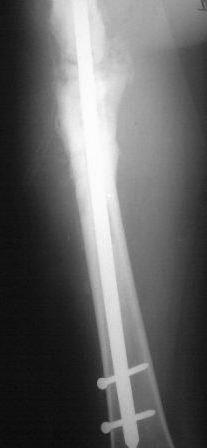

Представляю контрольные послеоперационные рентгенограммы. Во время операции была выделена зона перелома небольшим разрезом, произведена декортикация. Окончательный остеосинтез.

На снимках все выглядит хорошо, поздравляю. Декортикацию только делали напрасно, но уж что сделано, то сделано.

Спасибо! Для рассверливания канала предварительно из зоны перелома выполнили перфорацию сверлом диаметром 6 мм, т.к. на протяжении практически 10-12 см в зане перелома склерозированная кость с кистозными полостями. Из зоны перелома были удалены рубцовые плотные ткани. Окончательно формировали каналя с использованием полугибких риммеров. Канал рассверлили до 10 номера, гвоздь № 9 длиной 380 мм. Посев из зоны оперативного вмешательства отрицательный. Для контроля 3 суток назад посеяли отделяемое по дроенажу (геморрагическое). Дренаж удалили на 3-и сутки. насегодняшний день 6 сутки, заживление первичное. По окончании установки гвоздя в канал осуществили компрессию до уровня плотного соприкостновения костных отломков, после чего длокирование гвоздя. Визуально есть участок около 1,5-2 см где гвоздь визуализируется, но вспоминая длительный остемиелит от допонительного использования трансплантатов отказались.